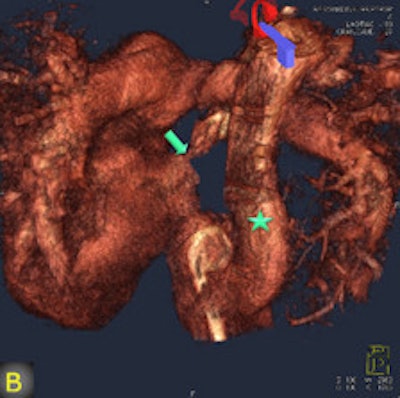

FD-CT, combined with image fusion to overlay 3D reconstructions on fluoroscopic images during catheter-based interventions, was useful -- and occasionally irreplaceable -- for deciphering the complex anatomy of congenital heart disease, wrote authors Dr. Martin Glöckler, Dr. Andreas Koch, and colleagues from University Hospital Erlangen in Erlangen, Germany.

"The fusion of 3D reconstructions with live fluoroscopic images during catheterization may help to find the ideal fluoroscopic angulation during catheter-based interventions, to achieve difficult vascular crossings by the wire or the catheter, to choose the most appropriate material for catheterization, and to define and control optimized positioning of implants such as stents or valve prostheses," Glöckler and colleagues explained.

"One unique feature of FD-CT is the possibility of merging 3D reconstructions with the real-time fluoroscopic image," a potentially useful way to identify ideal C-arm angulations for achieving wire passage for atypical vascular crossings, and to optimally depict the implant position of coils, plugs, stents, and valves," Glöckler and colleagues wrote. "In fact, image fusion of 3D reconstructed FD-CT images with the live fluoroscopic image was frequently rated as 'very useful' (57.4%)."